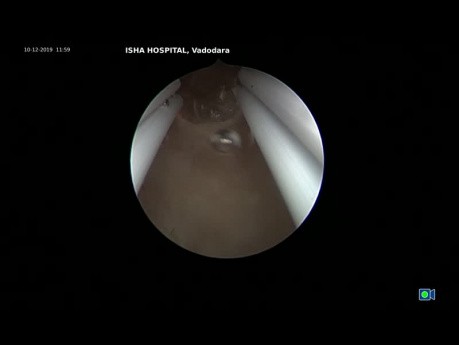

Histeroskopowa resekcja polipa

Histeroskopowa resekcja postmenopauzalnego polipa u asymptomatycznej pacjentki, u której stwierdzono również wypadanie narządu rodnego z cystocele. Użyto bipolarnego resektoskopu. Jama macicy jest przedzielona...